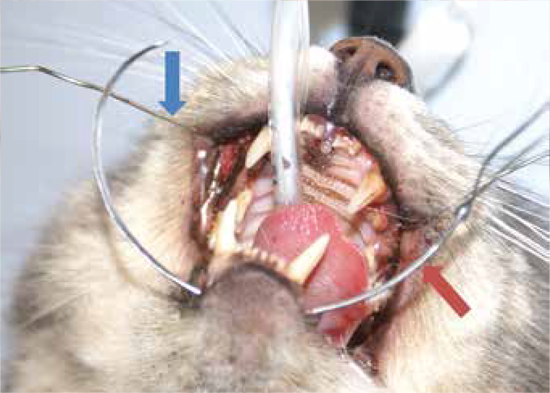

- Insertar un alambre de acero inoxidable de 20 ga. a través de la cavidad nasal entrando y saliendo por los agujeros hechos por el clavo. Figura 2; flecha azul.

- Enhebrar el extremo del alambre a través del ojo de una aguja de sutura curvada grande, que se inserta lo más cerca posible a la cara lateral del lado izquierdo de la mandíbula.

- Dirigir la aguja de manera ventral a la mandíbula y luego lateralmente hacia el lado derecho, saliendo en la ubicación contralateral correspondiente a su inserción. Figura 2; flecha roja.